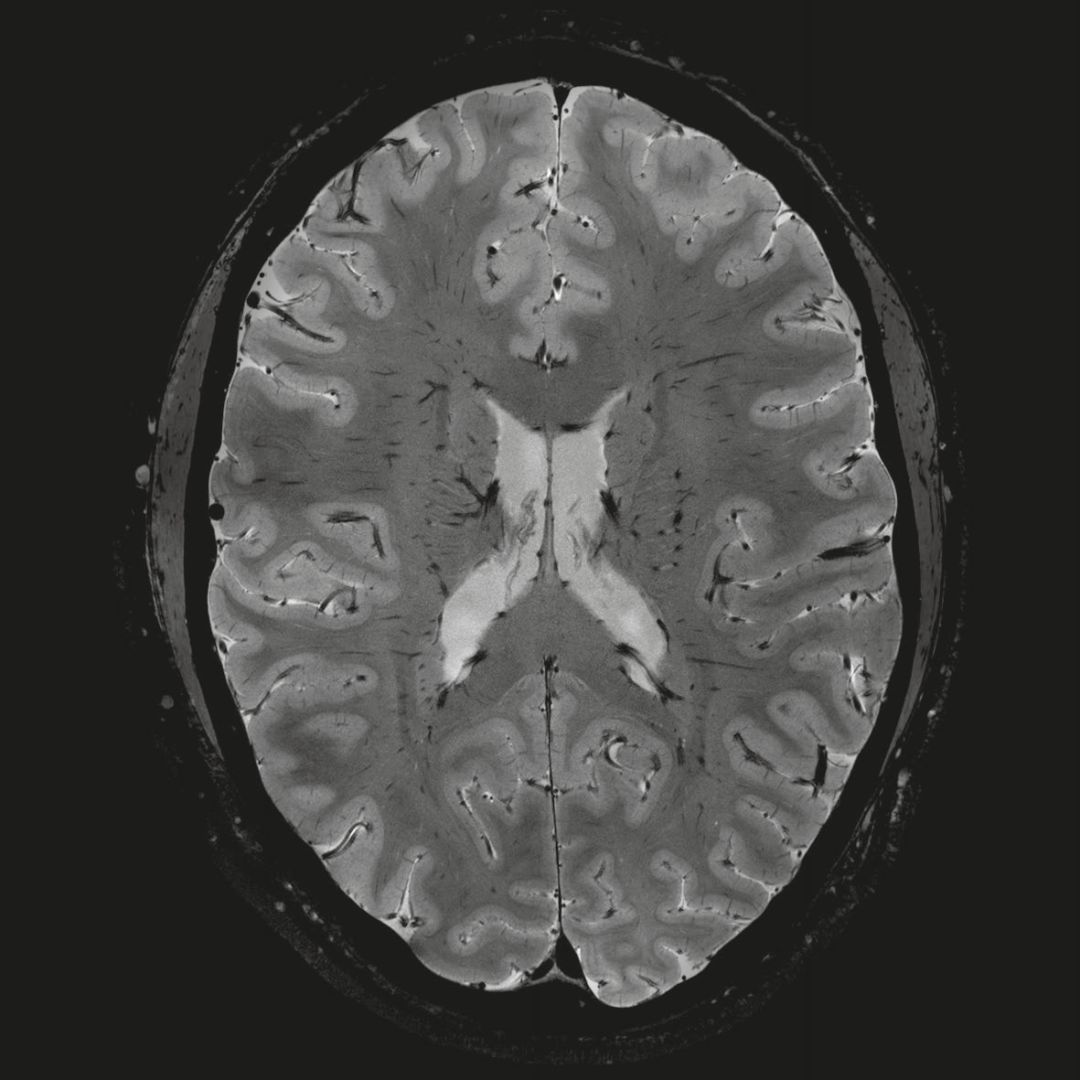

超精細(xì)的解剖細(xì)節(jié):T2對比

0.17 x 0.17 x 0.8毫米分辨率超高。